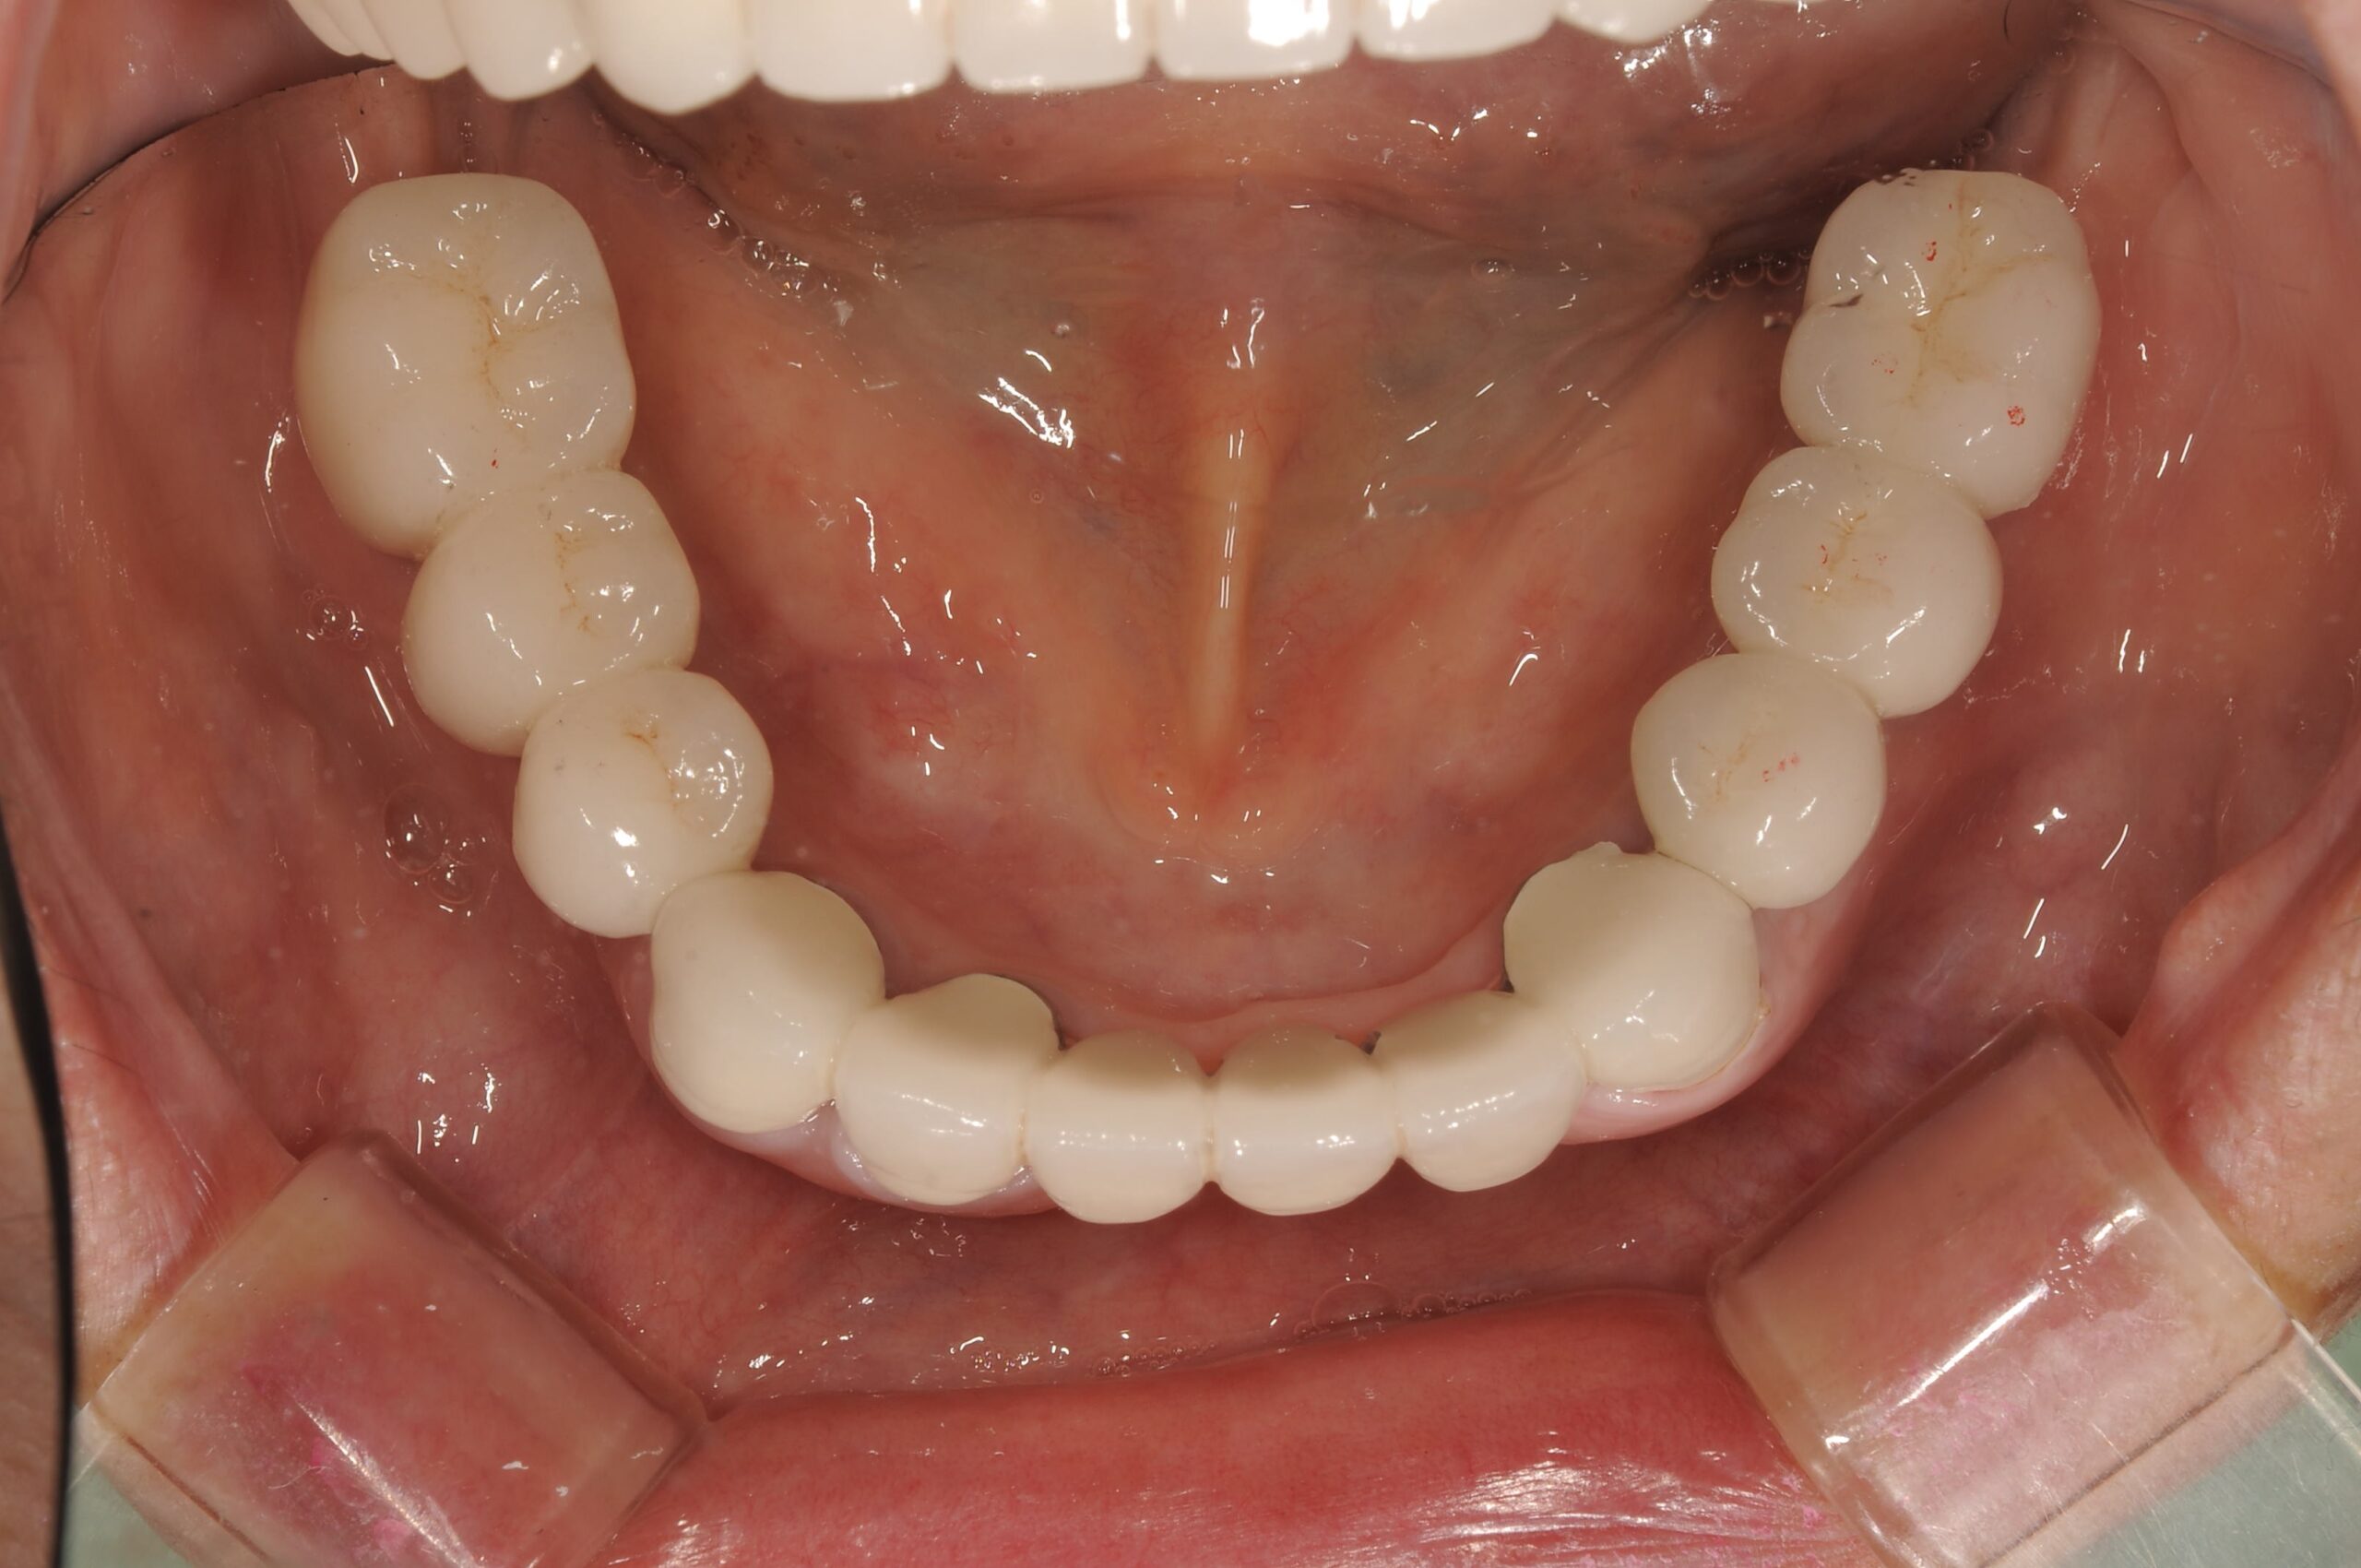

上顎の12本,下顎12本の固定式の歯が入り、なんでもおいしく食べられるようになられました。